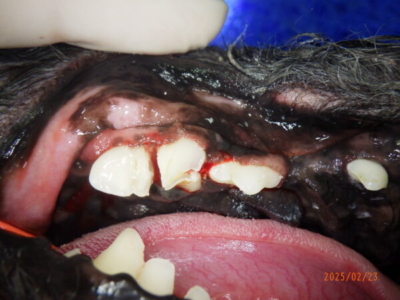

そして当日です。全身麻酔をかけて、たくさんついていた歯石を外すと・・・

かたちがおかしいと感じた右上顎第四前臼歯は、歯がかけて神経が出ている状態でした。

反対側、左上顎第四前臼歯は歯石をとるとこのような状態です。

左上顎第四前臼歯。